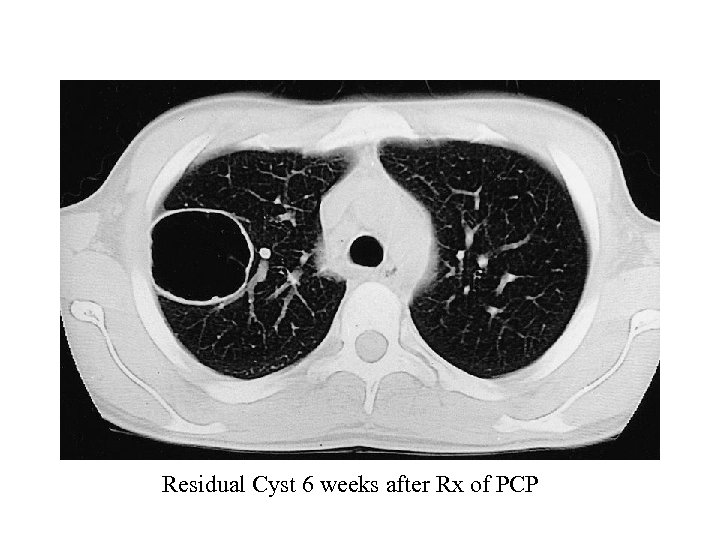

Pneumocystis Pneumonia – CXR typically bilateral interstitial infiltrates or normal (if mild) – Atypical presentations: nodules, blebs and cysts, asymmetric disease, upper lobe localization, and pneumothorax occur. – Pneumothorax in a patient with HIV infection should raise the suspicion of PCP – Cavitation, intrathoracic adenopathy, and pleural effusion are uncommon • presence might indicate an alternative diagnosis. – Approximately 13%– 18% of patients with documented PCP have another concurrent cause of pulmonary dysfunction (e. g. , TB, KS, or bacterial pneumonia) 11

Residual Cyst 6 weeks after Rx of PCP